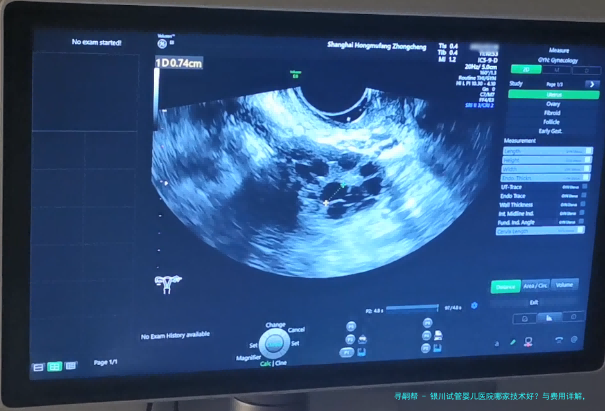

是动态数据,受患者岁数、病因、胚胎质量等多要点影响。银川主要生殖医学中心的临床妊娠率(移植后经B超认定怀孕的比率)在40-55之间,符合国内平均水平。宁夏医科大学总医院和银川市妇幼保健院因其例子量大、技术安定,统计常处在地区前线。但务必理解,是统计观点,个体情况需详细解析。

| 孕期早期监测(B超等) | 1500//td> | 800 | 1100 | 900-1300 |